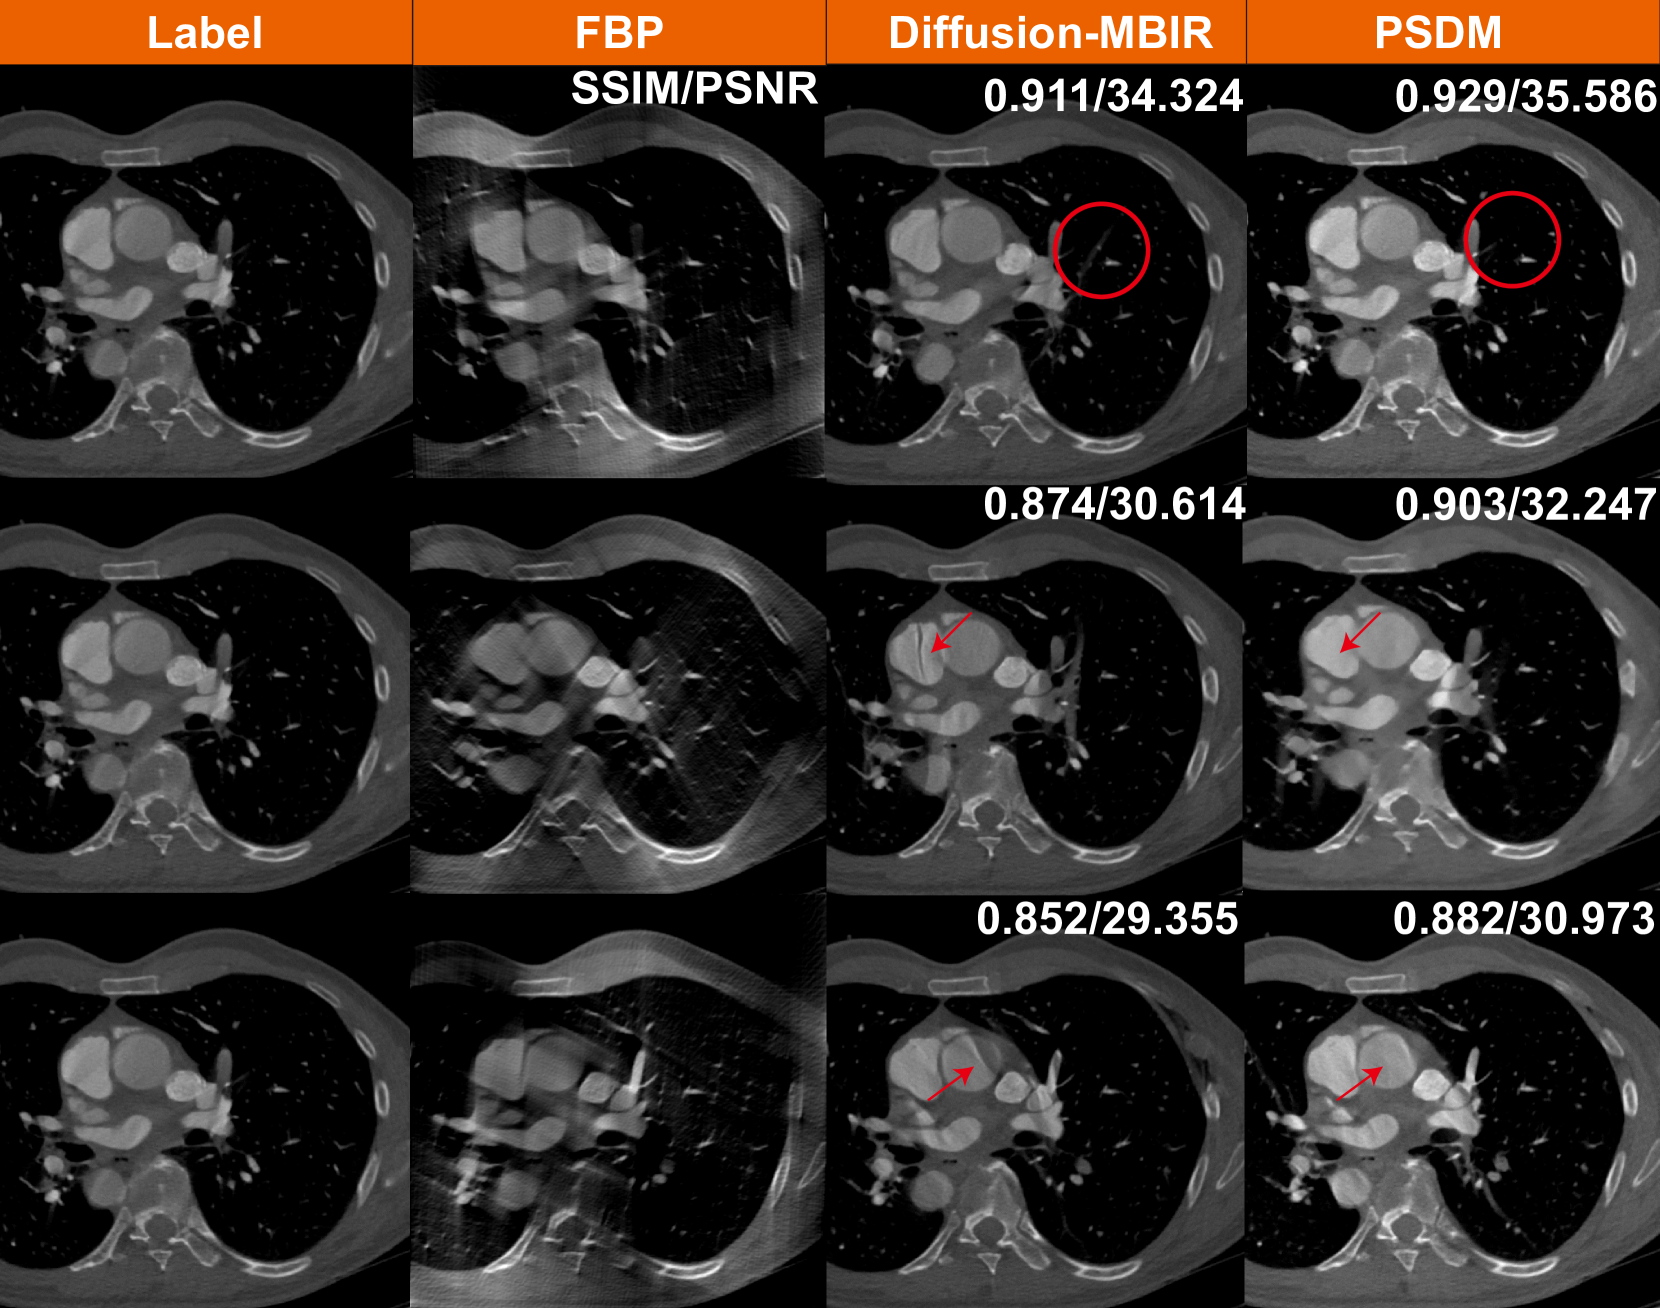

4.2.2 Clinical cardiac results

Generalization is a major issue for DLR-based methods, especially for models requiring supervised learning. If a model is trained strictly on data with a specific angle range (e.g., 0–120°), it will not generalize well to other angular ranges. However, different clinical situations might require different angular ranges. For instance, certain anatomical regions or pathologies are better visualized with a specific angle range. To further demonstrate the advantages of PSDM, the algorithm is applied to a real clinical cardiac dataset. With the approval of the Institutional Review Board of the University of Massachusetts, Lowell, a deidentified clinical cardiac CT dataset is obtained from a GE HD 750 scanner. The patient was scanned using axial mode. 1,520 projections are acquired over an angular range of 556° (\approx 1.54 rotations). Each projection row has 835 elements at 1.095 mm pitch. The source to the rotation center distance is 538.5 mm, and the source to the detector distance is 946.7 mm. Reconstruction is performed by FBP using equi-angular geometry, where the image size is set to 512×512512512512\times 512512 × 512 to accelerate the sampling process. Since the supervised learning-trained models (FBPConvNet and TomoGAN) usually can only process specific angle range, we compare only the two unsupervised learning methods: Diffusion-MBIR and PSDM. During the sampling stage, these two methods directly utilize the checkpoints trained on the aforementioned Stanford AIMI COCA datasets. Fig. 6 shows the 120-view limited-angle reconstruction images from different angular ranges. We find that both Diffusion-MBIR and PSDM produce consistent and apparently acceptable results. However, compared with the Diffusion-MBIR, the results produced by PSDM exhibit fewer limited-angle artifacts and appear to provide a more realistic representation. These differences can be seen in the areas and structures underscored by red circles and arrows. Specifically, in the atrial region denoted by the red arrow, PSDM produces more stable results, while Diffusion-MBIR still exhibits limited-angle artifacts in the atria.

Figure 6: Reconstruction results from a clinical cardiac CT scan, using different methods, each corresponding to different scanning angular ranges of 120°. The first row are reconstructions from spanning angles 0° to 120°, the second row are for 30° to 150°, and the third row are for 60° to 180°. The display window is [400400-400- 400 1500150015001500] HU.